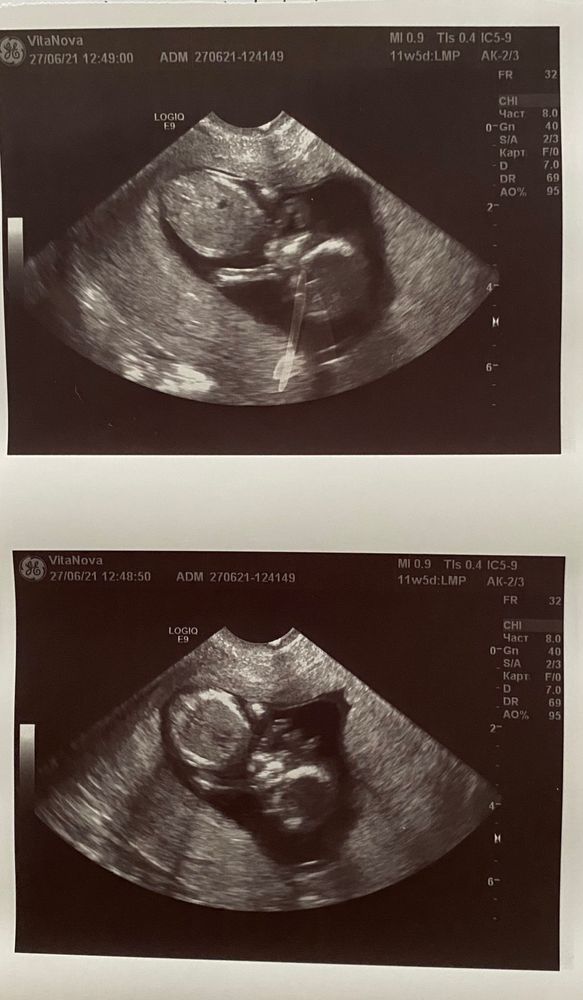

1-ый скрининг. Много букв. А это на любителя :)